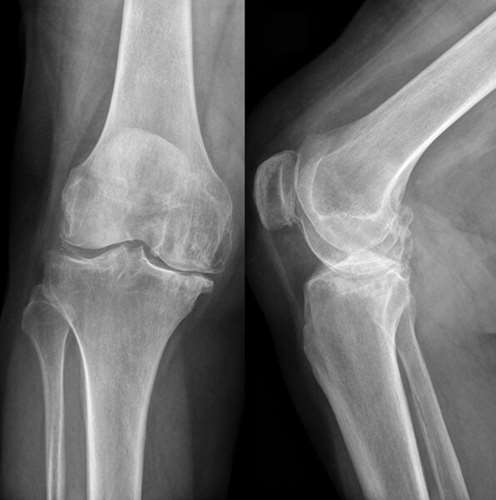

РОЗПІЗНАЙТЕ НА РЕНТГЕНОГРАМІ СУГЛОБ, ЩО СКЛАДАЄТЬСЯ З ТРЬОХ СУГЛОБІВ, ЯКІ МАЮТЬ СПІЛЬНУ КАПСУЛУ.

СУГЛОБ СКЛАДНИЙ. СУГЛОБОВА КАПСУЛА ТОНКА, УТВОРЮЄ БАГАТО СУМОК, ЯКІ СПОЛУЧАЮТЬСЯ ІЗ СУГЛОБОВОЮ ПОРОЖНИНОЮ. ЦЕ СПРИЯЄ ПЕРЕХОДУ ЗАПАЛЬНИХ ПРОЦЕСІВ (Є ДІАГНОЗ: БУРСИТ). ДЕ ВИ БАЧИТЕ ЦЕЙ СУГЛОБ.

СУГЛОБ СКЛАДНИЙ. УТВОРЕНИЙ СУГЛОБОВИМИ ПОВЕРХНЯМИ МЕДІАЛЬНОГО І ЛАТЕРАЛЬНОГО ВИРОСТКІВ, ЯКІ Є В ОБОХ КІСТКАХ, ЩО ЙОГО УТВОРЮЮТЬ. РОЗПІЗНАЙТЕ СУГЛОБ.

Запитання 61